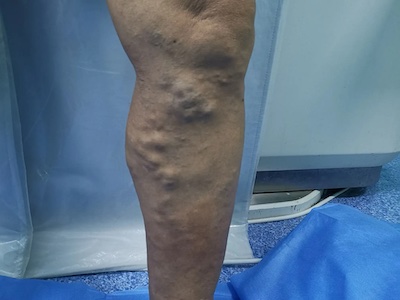

原发性大隐静脉曲张,又称为单纯性大隐静脉曲张,主要是由于静脉瓣功能不全、静脉壁薄弱等因素导致。可造成腿部酸胀不适、沉重、轻度疼痛,并伴有局部静脉隆起、扩张、迂曲等症状,严重时,可导致局部皮肤色素沉着、溃疡等情况发生。

原发性大隐静脉曲张开始时可无症状,随着静脉的扩张,因静脉外膜感受器受到刺激而有酸胀不适、沉重、轻度疼痛等症状,后期则以静脉曲张为主要表现,可在小腿前内侧出现浅静脉的隆起、扩张、迂曲,甚至蜷曲成团,站立时更为明显,有时还会蔓延至小腿后面。

此外,对于病程较长者,还会造成足靴区皮肤出现营养不良性变化,如皮肤萎缩、色素沉着,严重时还会造成局部溃疡的发生。

对于症状不明显、静脉曲张程度较轻的原发性大隐静脉曲张患者,可使用弹力绷带或弹力袜压迫疗法,或局部注射硬化剂治疗。对于有明显症状、且无手术禁忌者,建议遵医嘱尽早采取手术治疗,常用手术方式包括单纯曲张静脉剥脱、大隐静脉高位结扎剥脱等。